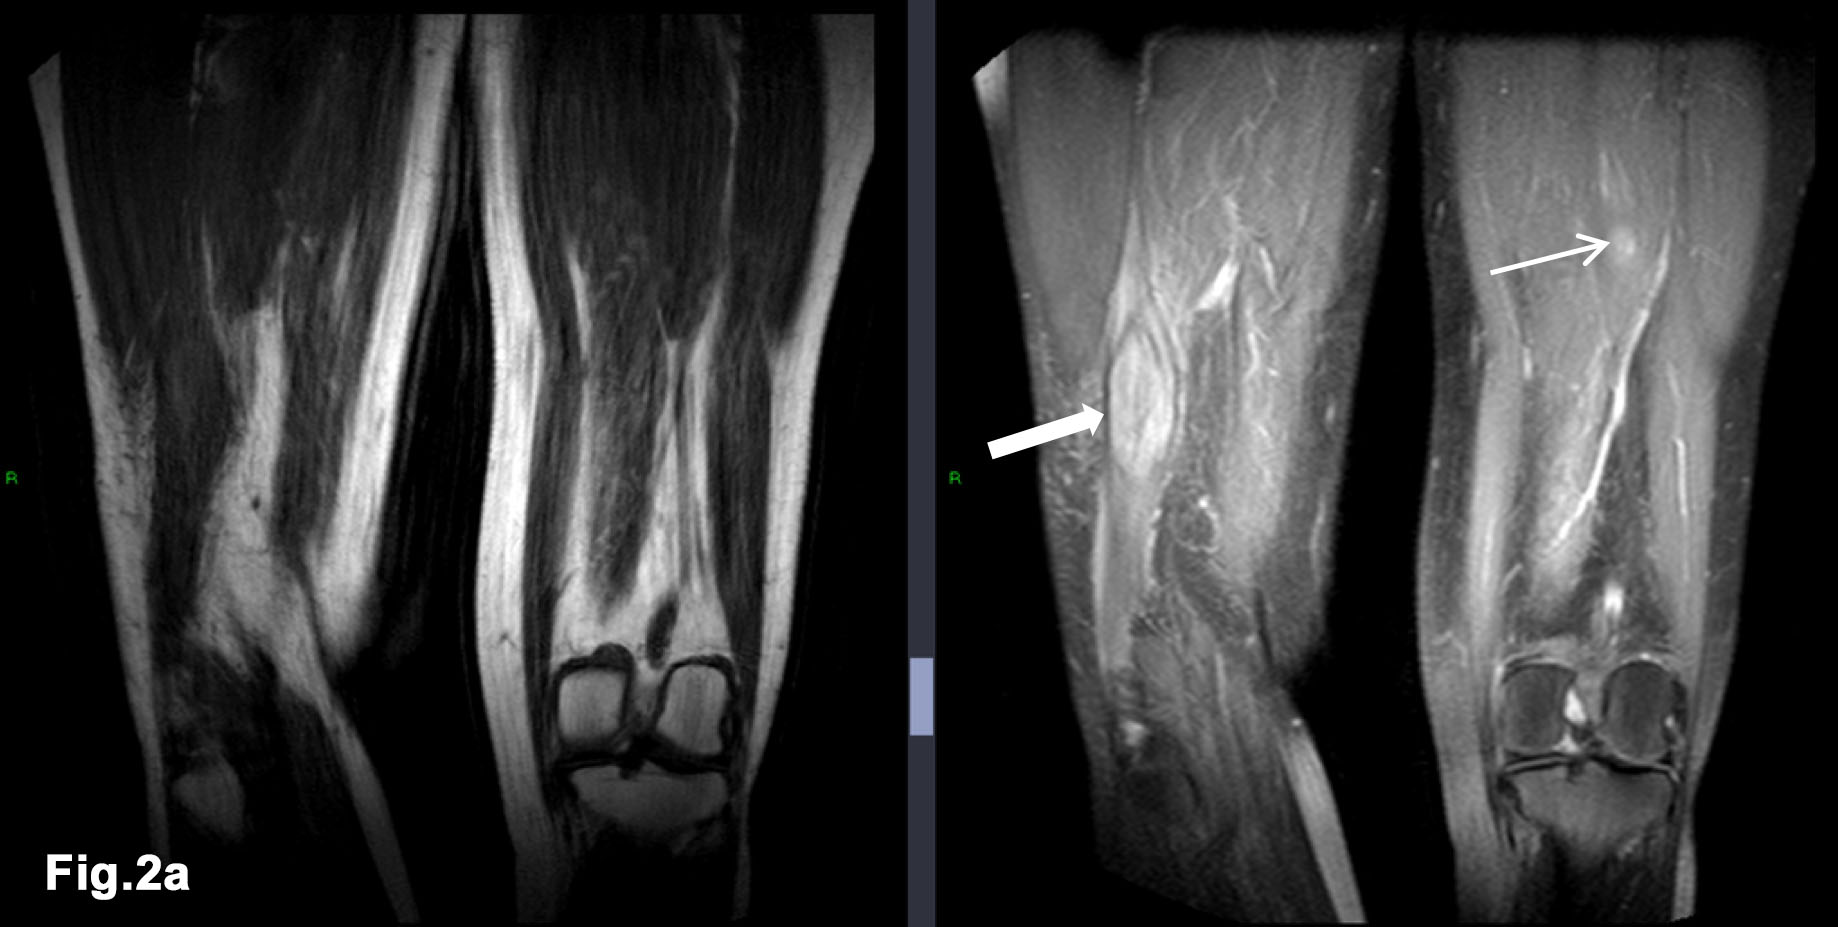

Figure 2 – initial external MR - confirms larger mass within right distal biceps femoris muscle (solid arrow) and demonstrates further, smaller mass between fat plans of left posterior thigh muscles (line arrow) - T1w and PDW DRI images (Fig 2a) - T1W FS Gadolinium enhanced MR – demonstrates enhancing intramuscular lesions with peripheral oedema (arrows) (Fig 2b)

- There was an abnormal soft tissue mass in the distal posterior thigh, related to the biceps femoris.

- MRI 2016 (Figure 2)

- Elliptical mass like lesion measuring 7.2 x 2.7cm on T1 weighted imaging which was isointense to normal muscle but demonstrates patchy, peripheral enhancement following gadolinium injection. The mass was within the short head of biceps femoris muscle.

- Another smaller similar lesion was noted within left thigh, measuring 2.9cm lying in the fat plane between posterior thigh muscles.